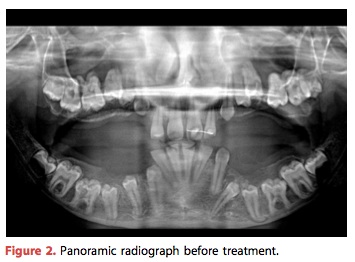

這是一個79歲的男性患者, 上顎是overdenture而下顎是4 implant supported fixed denture. 原本使用metal abutment cement zirconia prosthesis, 追蹤18個月後發現鬆動, 一拆掉發現zirconia有裂痕而且metal abutment有很嚴重的磨損. 後來就換成鈦金屬的bar加樹脂牙.